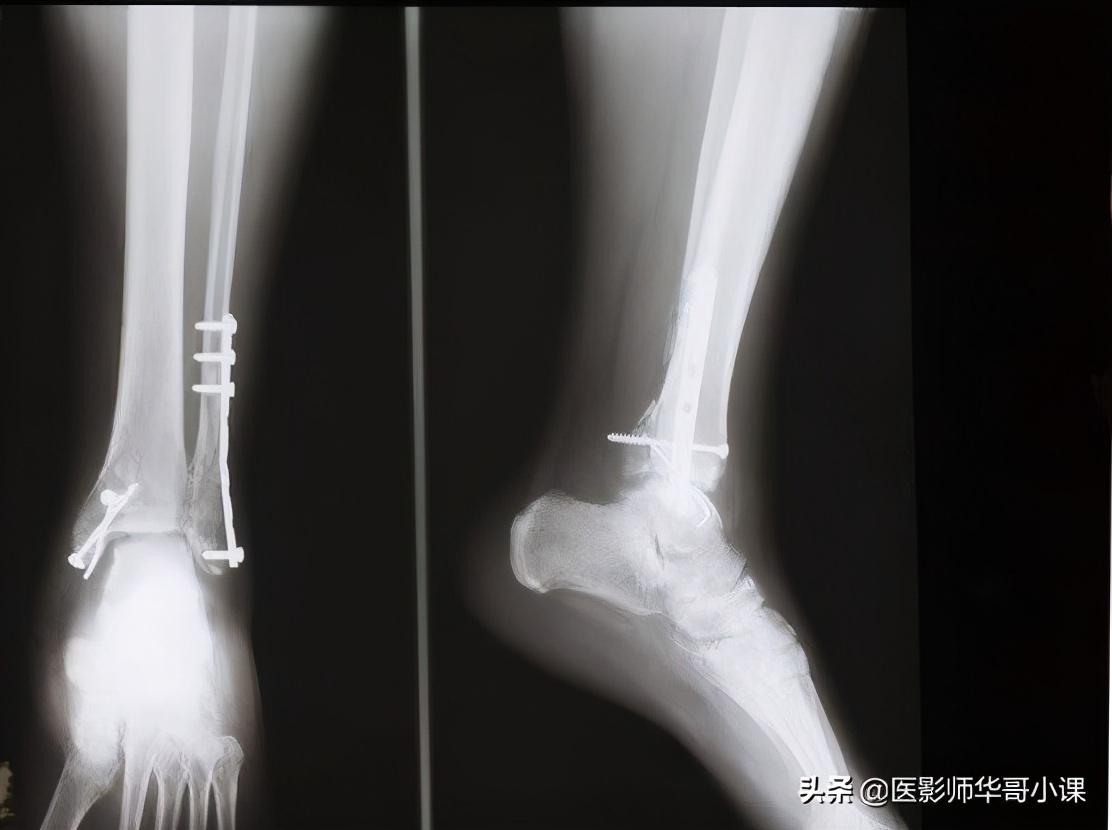

第四节 足与踝

1趾骨骨骺骨化中心往往为多个小骨化核,外缘不规则。第二,三,五趾末节趾骨骨骺的二次骨化中心可永不出现。

2.末节趾骨的远端稍肥大,边缘不整齐,为正常现象。

3.基节趾骨跖面肌腱附着处,在侧位片上表现为边缘不整齐。

4.趾骨和跖骨,这些小管状骨的继发骨化中心常由若干小骨块组成,在它们出现后若干年内都呈边缘粗糙的不规则阴影,第一趾跖关节处常有一个或两个籽骨,一个籽骨有时可分为两半,不可误为骨折。在发育期间,第五跖骨近端骺软骨外侧可能出现一个阶梯状二次骨化中心,多数为双侧,数年后与跖骨愈合,也可终生不愈合。

5.跖骨近端互相重叠,甚似骨折线,两个跖骨近端可能融合为一,而无跖骨功能不全的症状。

6.跖骨近端可有多余的化骨核,和掌骨一样。

7.舟状骨化骨核发生在生后六个月开始钙化,早期多不整齐或不规则,这种现象可能持续数月或数年之久,仅在一侧发生,在足舟骨结节处的副骨最为多见,一般为双侧性,少数单侧。

8.在舟距关节近端,距骨背缘上的皮雷氏骨,不要误认为碎骨。

9.距骨后结节下缘可能有一副骨即三角骨,这个副骨可能和距骨愈合,也可能是永远分离的。

10.骰骨的化骨核在早期是多个不规则小化骨核,楔状骨的化骨核在早期也可以是不规则的。

11.婴儿和儿童的跟骨后缘是不整齐的,跟骨结节的化骨核最初多为不整形的分节状,以后又较其它部分致密,均为发育中的正常现象。跟骨体偶可有两个独立的或多个骨化中心,二者之间的软骨带在融合前颇似骨折线。

12.跟骨滑车突顶端的二次骨化中心,在外旋和内翻45度角摄片时很似碎骨片。

13.七岁以上儿童的足部侧位上,在跟骨滑车的骨质中能见到一个圆形或三角形的假性囊肿样透亮阴影,此因骨松质稀疏所致。

14.载距小骨足副骨中极其罕见的一种,发生于跟骨载距突的上方。

15.胫骨远端可能出现一个单独分离的内踝化骨核,腓骨外踝部也可有一个单独的化骨核。

16.胫骨骨干远端外侧面面有一条沟槽即腓骨切迹。